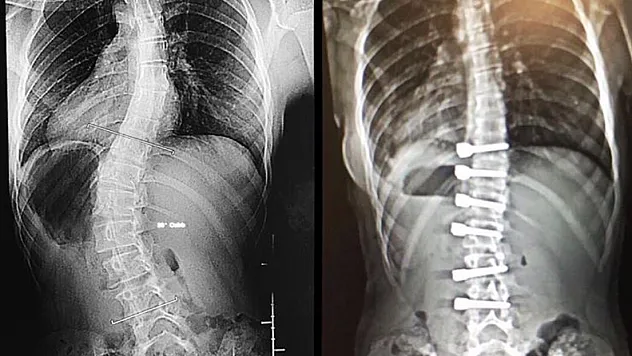

'Duruş bozukluğu skolyoz işareti olabilir'

'Duruş bozukluğu skolyoz işareti olabilir”